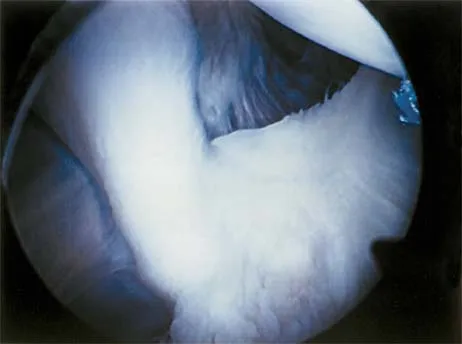

A 15-year-old girl reports a 6-month history of activity-related knee pain and swelling. A radiograph, MRI scan, and biopsy specimen are shown in Figures 21a through 21c. What is the most likely diagnosis?

The epiphyseal location on the radiograph and MRI scan and the histologic findings of polyhedral cells separated by a chondroid matrix with pericellular, lattice-like "chicken wire" calcification all suggest chondroblastoma. Although giant cell tumors of bone typically occupy an epiphyseal location, they are rare in children and when present are often metaphyseal in skeletally immature patients. Enchondromas and osteoblastomas are generally metaphyseal and, along with giant cell tumors, have very different histology than seen here. Chondromyxoid fibromas are typically metaphyseal in location. Huvos AG: Bone Tumors: Diagnosis, Treatment, and Prognosis. Philadelphia, PA, WB Saunders, 1991, pp 295-313.